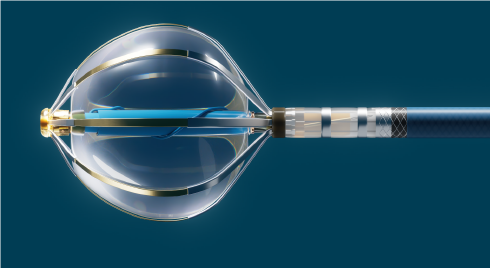

Neben der pharmakologischen Behandlung des Vorhofflimmerns gewinnt die Verödungsbehandlung (Katheterablation) infolge ihrer höheren Effektivität in der Unterdrückung des Vorhofflimmerns immer mehr an Bedeutung.

Die Katheterablation hat zum Ziel, durch das gezielte Setzen von Verödungszonen Barrieren aufzubauen, um das Auftreten und die Aufrechterhaltung von Vorhofflimmern zu verhindern. Diese Barrieren werden in der linken Herzvorkammer in aller Regel um die Lungenvenen (Pulmonalvenen) gezogen, um die Störfeuer aus diesen Venen zu blockieren. Bei langanhaltendem Vorhofflimmern (persistierendes Vorhofflimmern) können bei Bedarf zusätzliche punktuelle bzw. lineare Verödungszonen mit der Ablation („Substratmodifikation“) geschaffen werden, um das Vorhofflimmern nachhaltig zu beeinflussen.

Die größte Erfahrung gibt es heute mit der Hochfrequenzstrom-Ablation von Vorhofflimmern. Über einen Elektrodenkatheter werden mit Hilfe von Hochfrequenzstrom im linken Vorhof punktförmige Verödungszonen so gesetzt, dass sich zusammenhängende Linien bilden, die zum Beispiel die Pulmonalvenen umschließen und komplett isolieren.

Anschließend werden von der rechten Leiste aus mehrere millimeterdünne Kunststoffschläuche (Elektrodenkatheter) zum Herzen vorgeschoben und nach Punktion der Vorhofscheidewand (transseptale Punktion) in den linken Vorhof platziert. Mit diesen Kathetern kann der Kardiologe die elektrischen Ströme, die durch das Herz fließen, aufzeichnen und beurteilen. Die eigentliche Behandlung erfolgt dann mit dem Ablationskatheter, dessen Spitzenelektrode mittels Hochfrequenzstrom auf eine Temperatur von 60-70 Grad Celsius erwärmt wird. Dies ermöglicht eine Punkt für Punkt-Verödung von Herzmuskelzellen, sodass eine Isolationslinie entsteht, die die Ausbreitung von störenden elektrischen Impulsen unterbricht und dadurch das Vorhofflimmern verhindert. Mit Hilfe modernster Technologien, die ohne röntgenologische Kontrolle eine exakte dreidimensionale Positionsbestimmung der Elektrodenkatheter ermöglichen, können die einzelnen Verödungsimpulse exakt gesetzt werden.

Neueste Katheter-Techniken erlauben die Bestimmung des Anpressdruckes der Elektrode an der Vorhofwand. Dies erlaubt eine effektive und sichere Abgabe der Energie zur Verödung. Dieser Teil der Ablationsbehandlung dauert etwa 1-1,5 Stunden. Der Arzt kann dabei durch die Änderung der elektrischen Potenziale des Herzens erkennen, wie wirksam die Isolation der Lungenvenen ist. Das Behandlungsziel ist erreicht, wenn alle vier Pulmonalvenen isoliert, das heisst elektrisch komplett vom linken Vorhof getrennnt sind. Falls nach einer 30-minütigen Wartephase die Lungenvenen stabil elektrisch isoliert bleiben, werden die Katheter aus dem Herzen zurückgezogen und der Patient wird noch im Katheterlabor allmählich wach. Die weitere Behandlung erfolgt dann wieder auf der Normalstation, wobei der Patient bis zum nächsten Morgen Bettruhe zur Vermeidung von lokalen Nachblutungen in der Leiste einhalten sollte.